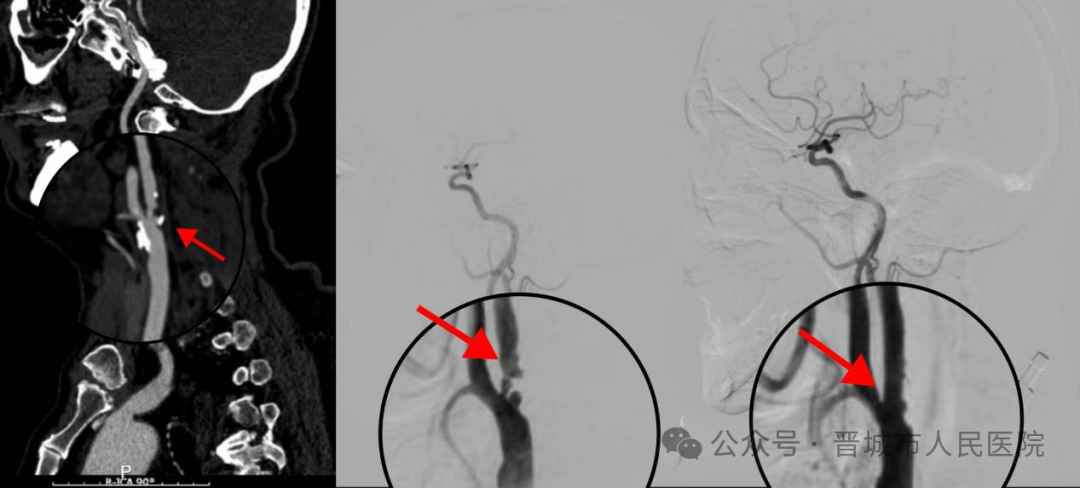

(图一是介入手术前的头颈部CTA影像,箭头所指处为狭窄部位;图二是手术前DSA影像;图三是支架术后DSA影像,血管狭窄明显改善)

经过周密的术前准备,包括双重抗血小板(阿司匹林、氯吡格雷)及他汀类药物治疗,手术于今日在局部麻醉下进行。术中,杨丰兵主任凭借精湛的技术,成功将一枚支架精准植入右侧颈内动脉狭窄处,瞬间重建了血流通路。整个手术仅耗时约1小时20分钟,患者全程清醒,无不适反应。术后造影显示血管狭窄解除,血流通畅。